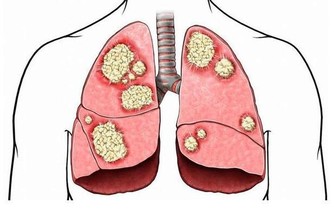

主要原因是,隨著腎功能的減退,腎臟的溶質清除率下降和某些肽類激素的滅活減少,造成多種毒素在血液和組織中蓄積,最常見的毒素就是尿素等。

在口腔中,因為唾液中的尿素被分解為氨,故病人呼出的氣體有尿味。

這種氣味的濃淡隨病情的進退而變化,在病情好轉時,口中尿味淡些,病情加重時尿味變濃。